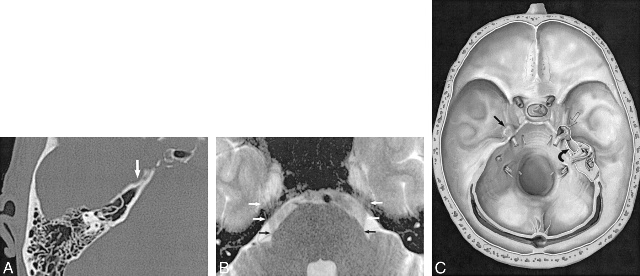

3. 三叉神经根受压的判断观察血管与三叉神经的解剖关系,由于侧卧位可引起小脑动脉移位,因此距三叉神经根1~2mm的血管均视为与神经有接触,特别是神经上有压迹或神经被推移和扭曲者更是可靠证据。下面部疼痛患者,是由于三叉神经根上前或后部受小脑上动脉压迫;而上部疼痛者则为神经根下外部受小脑前下动脉压迫。

4. 微血管减压确认血管压迫三叉神经根后,用长柄微型剥离子把血管从神经上分开,在三叉神经前方垫入小块明胶海棉。取1cm×0.5㎝涤纶片,两端用剪刀修成锐角,在明胶海绵和三叉神经根之间插入,并向后环绕神经,用一枚银夹把涤纶片两端对合,使之如“领套”状围绕桥脑旁的三叉神经, 以便与周围的血管隔离。也可用涤纶片衬垫在血管和神经之间,生物胶固定之。